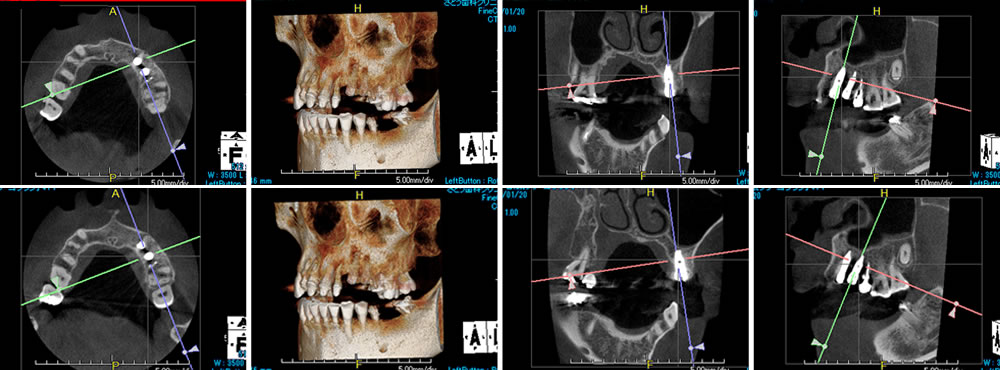

【CT画像(術前)2016年10月24日】

【CT画像(術後)2017年1月20日】

その後、抜歯した部分にインプラント体(3番目:半径3.75mm×11.5mm スプラインHAインプラント Zimmer社 、4番目:半径3.75mm×10.0mm スプラインHAインプラント Zimmer社)を通法に従い埋入し、ヒーリングキャップを締結しました。

インプラント周囲の骨がきちんと結合するよう、インプラント体と骨とのスペースには骨充填材(セラソルブ)を填入し、縫合しました。粘膜の治癒を待ち、1週間後に抜糸を行いました。